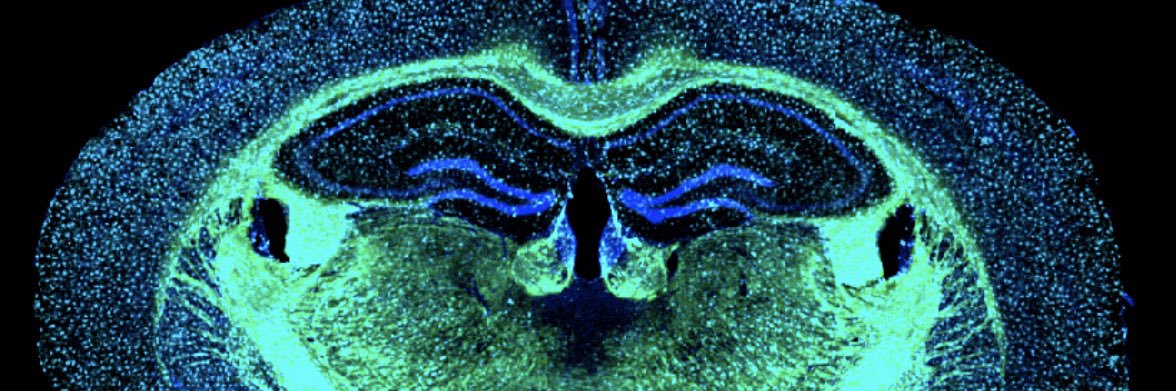

With support from a $4M grant, @Zuloaga_lab is leading a new study into how #menopause impacts #AlzheimersDisease, and if an estrogen therapy that targets the brain could help protect against #dementia. #AlzheimersAwarenessMonth albanymed.org/news/4m-nih-gr…